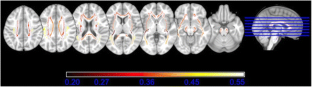

Both HIV disease and advanced age have been associated with alterations to cerebral white matter, as measured with white matter hyperintensities (WMH) on fluid-attenuated inversion recovery (FLAIR) magnetic resonance imaging (MRI), and more recently with diffusion tensor imaging (DTI). This study investigates the combined effects of age and HIV serostatus on WMH and DTI measures, as well as the relationships between these white matter measures, in 88 HIV seropositive (HIV+) and 49 seronegative (HIV−) individuals aged 23–79 years. A whole-brain volumetric measure of WMH was quantified from FLAIR images using a semi-automated process, while fractional anisotropy (FA) was calculated for 15 regions of a whole-brain white matter skeleton generated using tract-based spatial statistics (TBSS). An age by HIV interaction was found indicating a significant association between WMH and older age in HIV+ participants only. Similarly, significant age by HIV interactions were found indicating stronger associations between older age and decreased FA in the posterior limbs of the internal capsules, cerebral peduncles, and anterior corona radiata in HIV+ vs. HIV− participants. The interactive effects of HIV and age were stronger with respect to whole-brain WMH than for any of the FA measures. Among HIV+ participants, greater WMH and lower anterior corona radiata FA were associated with active hepatitis C virus infection, a history of AIDS, and higher current CD4 cell count. Results indicate that age exacerbates HIV-associated abnormalities of whole-brain WMH and fronto-subcortical white matter integrity.